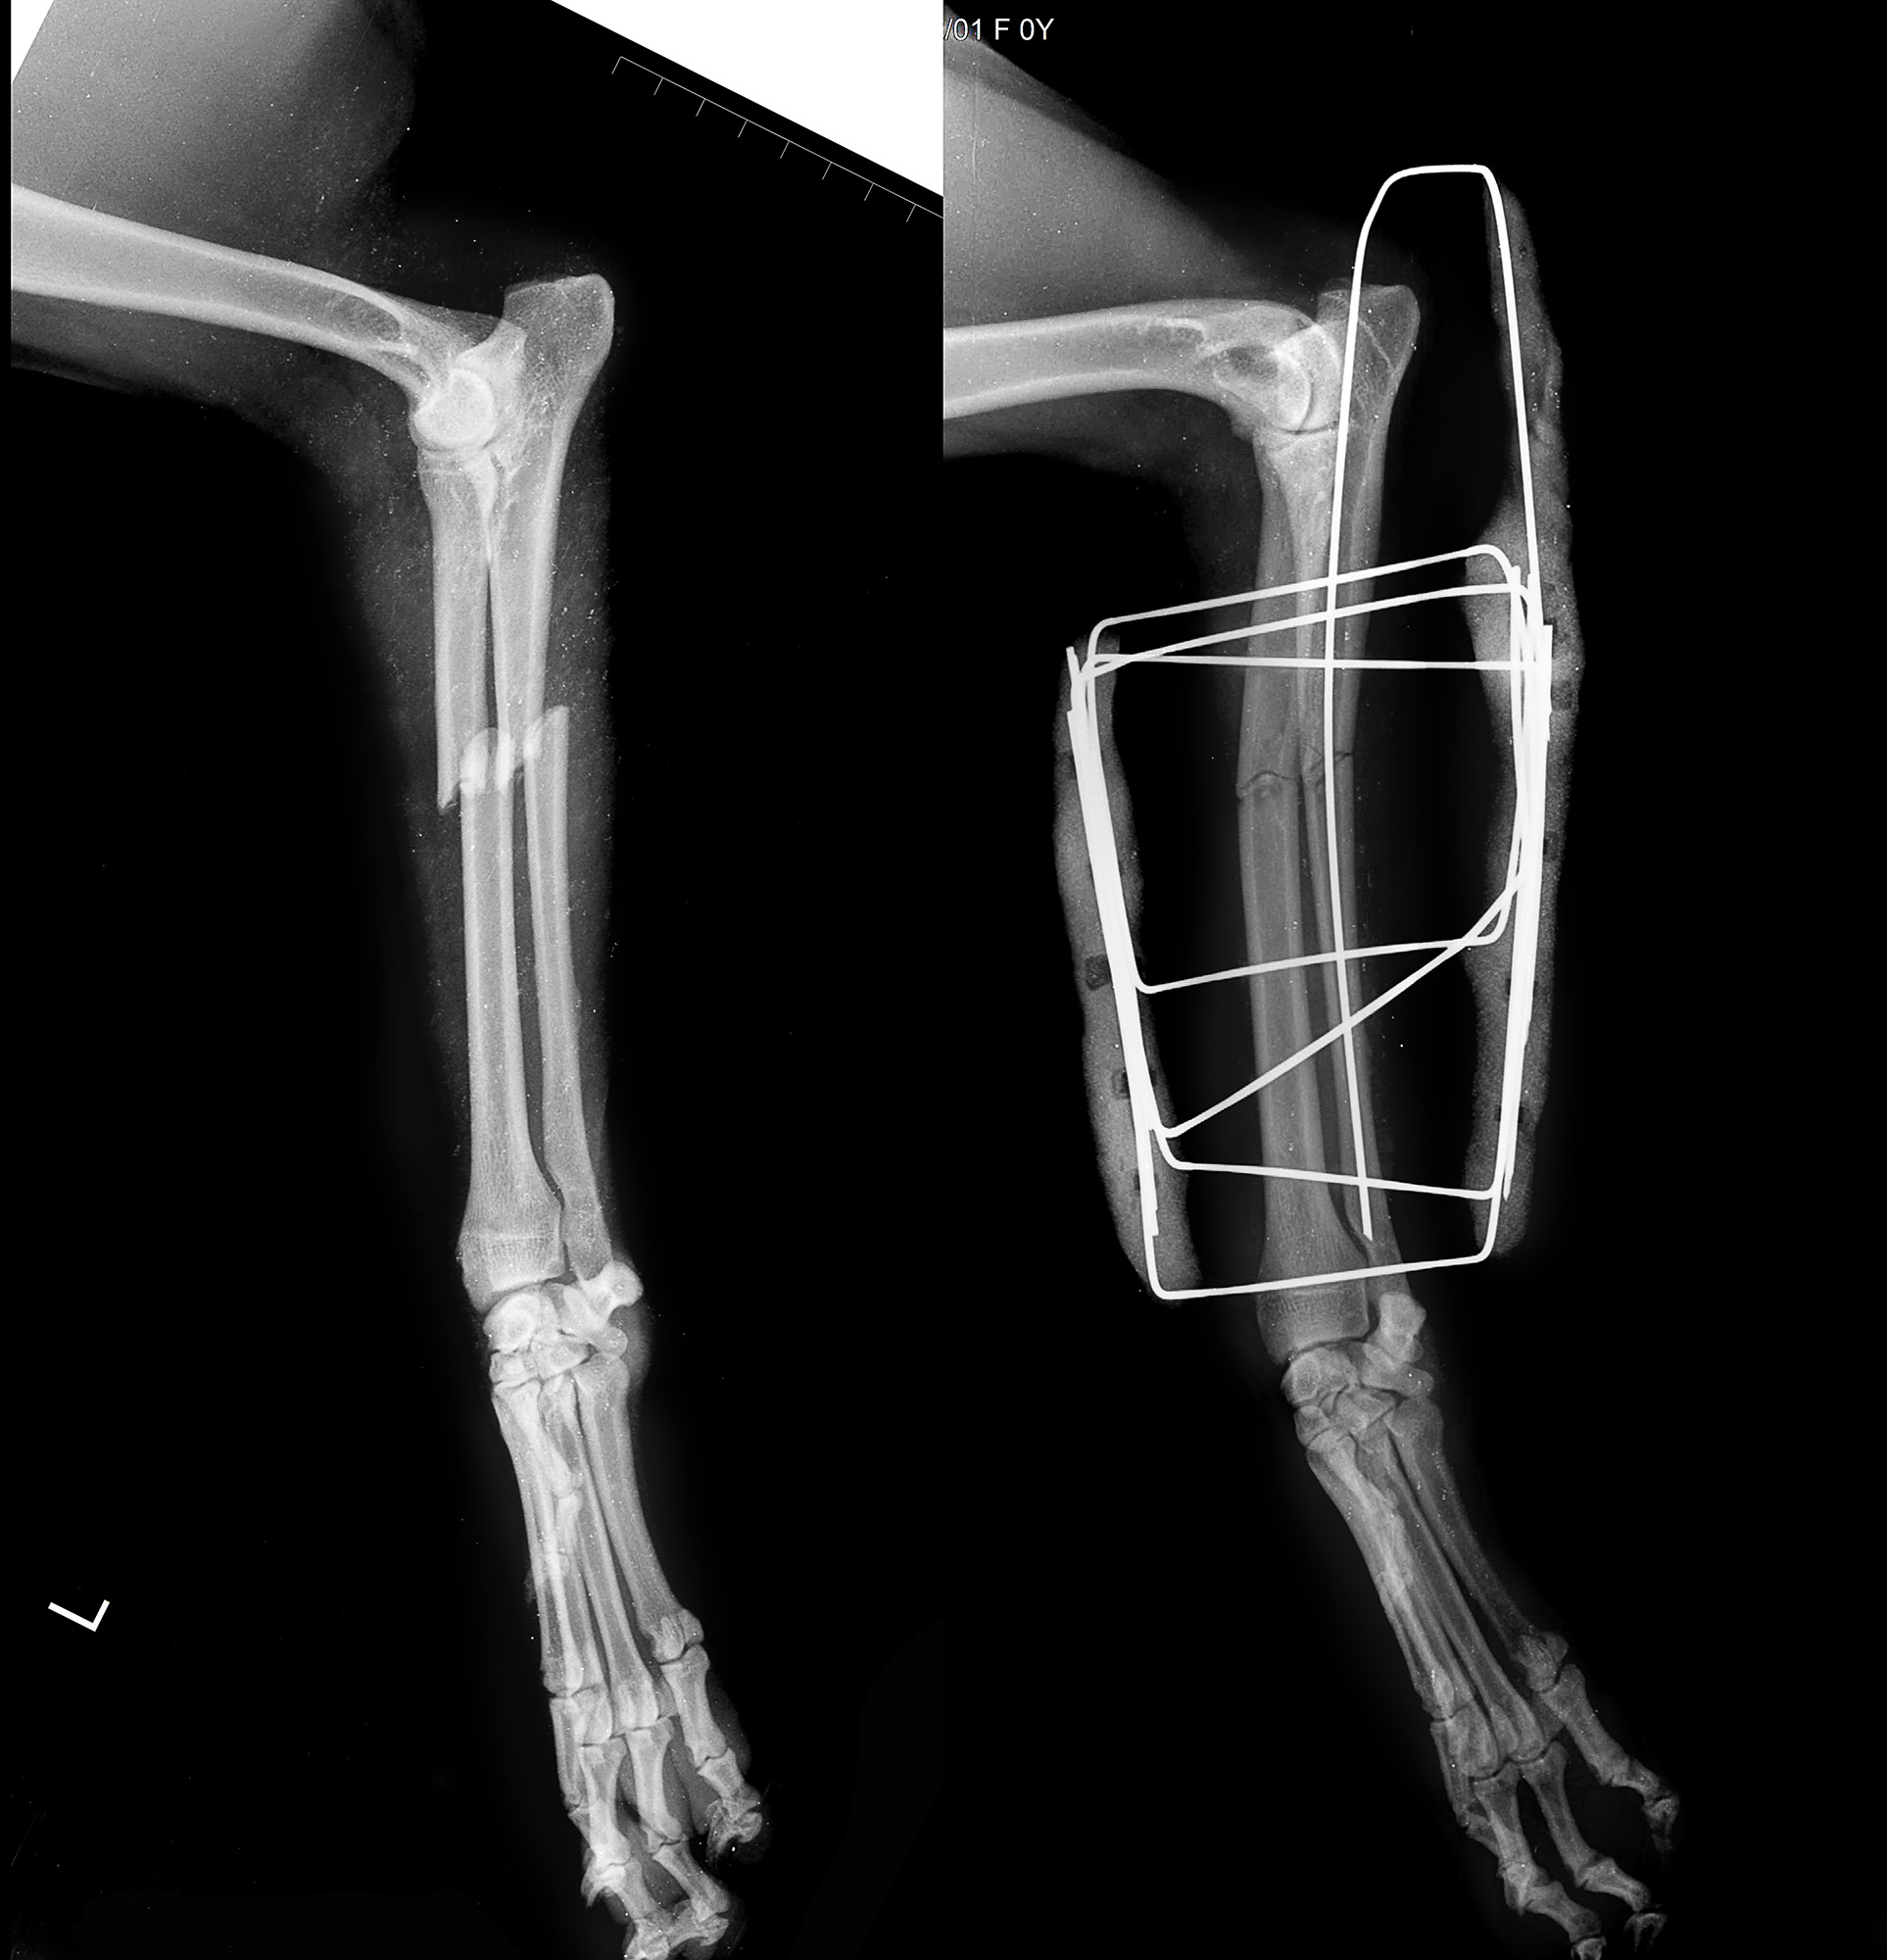

Рентгеновские снимки перелома лапы у кота: диагностика и лечение